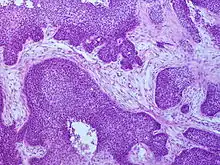

_squamous_cell_carcinoma_histopathology.jpg.webp)

Medical history, physical examination and medical imaging may suggest a squamous cell carcinoma, but a biopsy for histopathology generally establishes the diagnosis. TP63 staining is the main histological marker for Squamous cell carcinoma. In addition, TP63 is an essential transcription factor to establish squamous cell identity.[12]